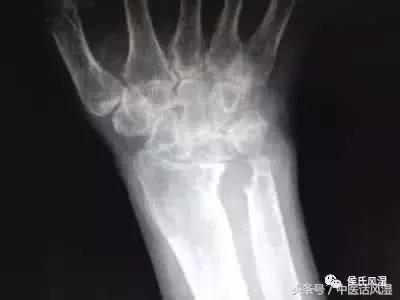

高雪娟是一名典型的类风湿病患者,中心上下的医护人员对她的病情记忆犹新:推着轮椅来到医院,双手双脚严重畸形,全身多处肌肉萎缩,膝盖红肿,并伴有肾功能不足等并发症,生活根本无法自理,还要麻烦年迈的婆婆照顾自己。一提起病情,婆婆更是老泪纵横,17年间,陪着儿媳遍寻名医良药,始终没能让病情有所好转,婆媳俩几乎对治疗绝望了,以致于多次听说侯氏疗法也没能前来就诊。

针对高雪娟的病情,南京侯氏的医生迅速按照侯氏疗法的体质分型,确定了高丽娟的体质特征,再从调整体质入手,施以特色腧疗养脏、募疗调息、通调三焦,而后从补肾入手,运用九宫回阳等方法补阳气,配合系统治疗,逐步缓解病痛、改善病症,最终使患者成功摆脱轮椅。2011年中秋,恰逢侯氏疗法创始人侯丽萍教授莅临南京,逐渐好转的高雪娟特地制作了一面锦旗,激动地献给自己心目中的恩人侯丽萍教授。如今,临近年底,高雪娟早已康复出院,相信目前的她一定可以轻松地照顾家人,开心地迎接这个久违的新年。

患者出院后,我中心客服部定期回访,患者双膝双腕关节无肿胀,行走自如,病情无反复,生活完全能够自理,料理家务、照顾家人都没有问题。